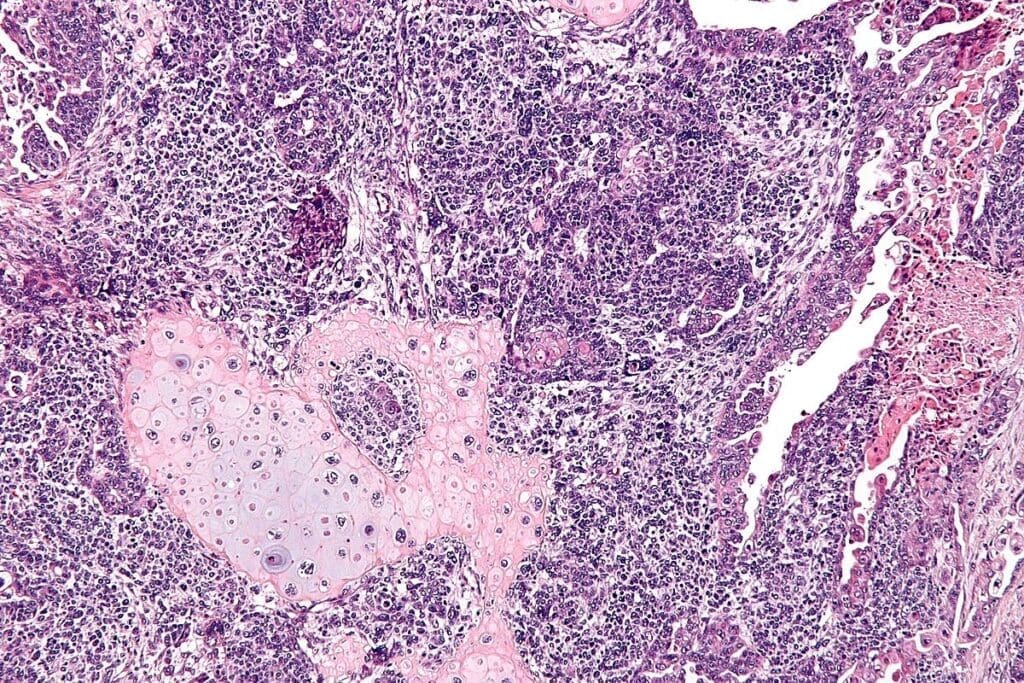

Major Types of Rhabdomyosarcoma and Their Predilection Sites

Rhabdomyosarcoma is divided into subtypes based on how they look under a microscope and their genetic makeup. Knowing these differences helps doctors treat the disease better and predict how it will progress.

Alveolar Rhabdomyosarcoma

Alveolar rhabdomyosarcoma is more common in teens and young adults. It often affects the arms, trunk, and the area around the anus. This type grows fast and has specific genetic changes.

Pleomorphic rhabdomyosarcoma is rare and aggressive, mainly found in adults. It can appear anywhere in the body, like the arms and trunk. It’s known for its varied cell types.